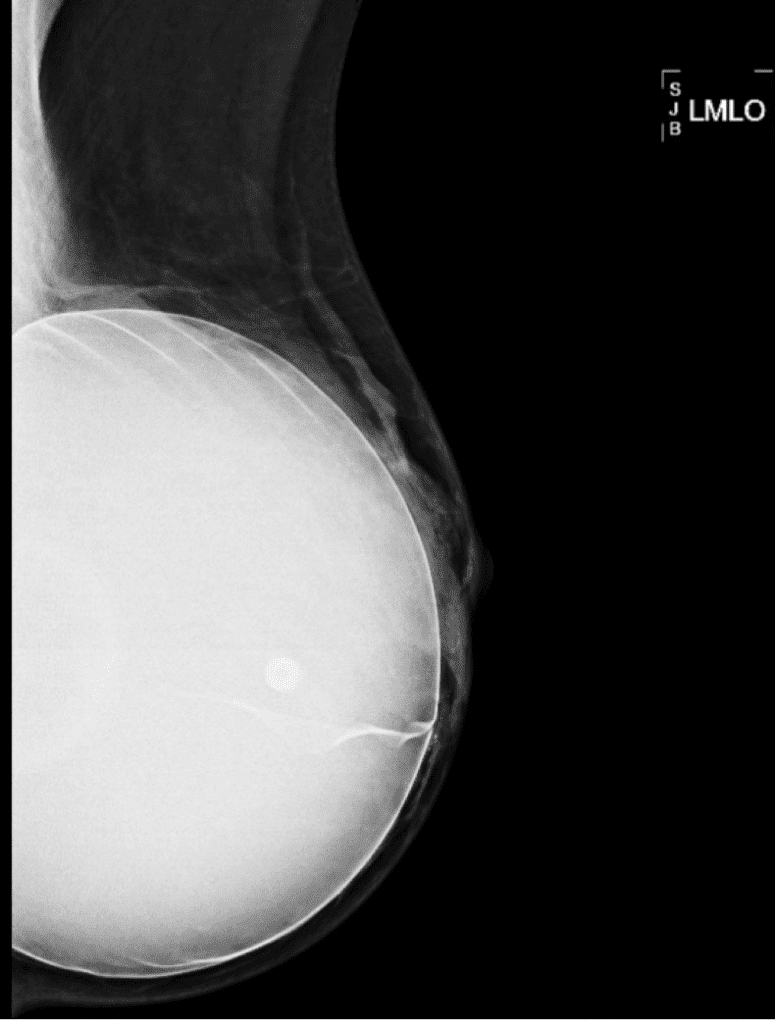

The implant in the left mammogram picture has a saline valve visible whereas the silicone implant on the right does not.

The smallest implants generally are 125 ml size, with the largest silicone 800 ml and largest saline 960 ml.  “Extra large” implants result from overfilling of saline implants.  Larger size implants likely correlate with increasing challenge with baby latch, positioning, and milk transfer.  In addition, they may place pressure on native glandular tissue, leading to attenuation (decrease) over time.  These larger implants also may contribute to nerve traction and reduced sensitivity of the nipple, similar to known phenomena with naturally large breasts.

This large implant that a patient had for 10 years shows how the native breast tissue can atrophy (decrease in size/function) over time from chronic pressure.